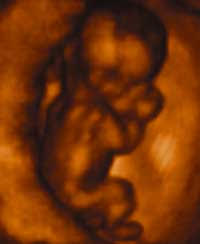

Fetal Development

Science proves that human life begins at conception (fertilization) when a genetically unique human being comes into existence, with his own genetic code.

Visit the Endowment for Human Development (EHD) to see the biology of development in the womb.